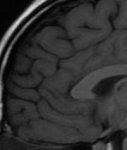

На МРТ мозг одинаковый. Это нажбровные дуги крупнее только и всего.